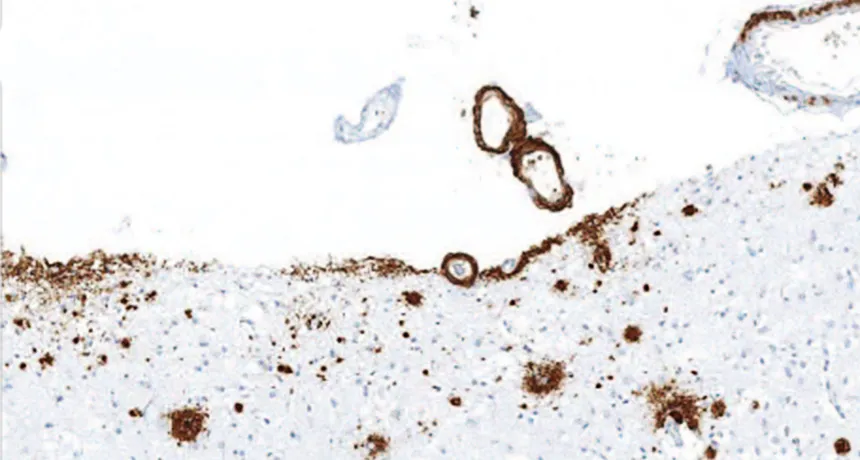

BUILDUP Amyloid-beta (brown) accumulated in the front of the brain in a person who received injections of cadaver-derived growth hormone as a child, suggesting that the injections were contaminated with A-beta.

Z. Jaunmuktane et al/Nature 2015

That exact scenario may have occurred in people who received injections of growth hormone derived from cadaver pituitary gland tissue, scientists report online September 9 in Nature. A postmortem study of eight such people who died between the ages of 36 and 51 found that four had substantial amyloid-beta buildup in their brains, a sign of Alzheimer’s disease.

The patients had all acquired Creutzfeldt-Jakob disease from prion-contaminated injections. Finding A-beta deposits in these relatively young brains suggests that those contaminated injections may have been laced with A-beta prions, too.